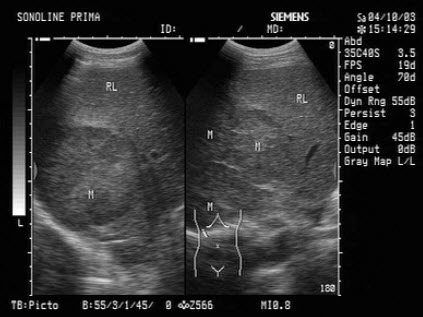

30、单项选择题

女性,26岁,停经29周,产前B超检查如图,超声诊断为()

A.胎盘早期剥离

B.正常中期妊娠

C.胎儿脐带绕颈

D.胎儿畸形,腹壁裂

E.畸胎瘤